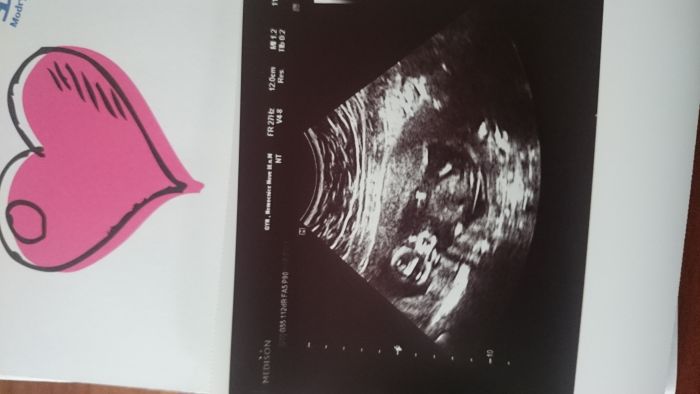

Ahoj holky, tak mám dnes za sebou 1.screening.Miminko sebou pěkně házelo, mávalo ručičkama...bylo to moc krásné. Pohlaví nám neřekla, .. a ani nenaznacila,tak musím počkat. Jinak máme 68 mm,NT 1,47mm a nosní kustka plus.Termin posunut z 15.4 dle ms na 18.4.Pridavam fotku našeho ufounka